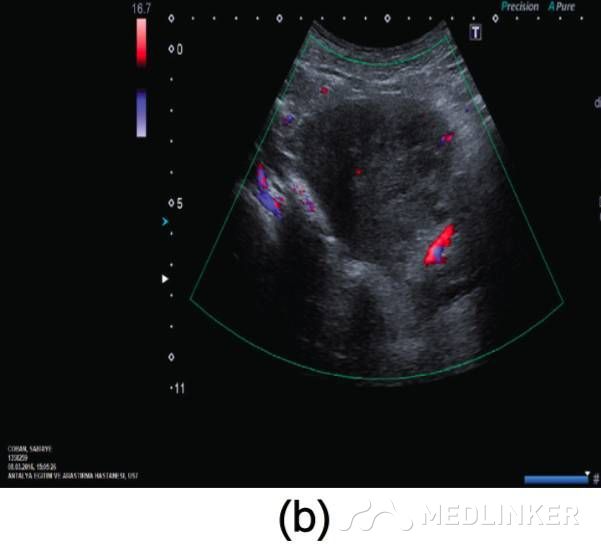

患者35岁,G2P1A1,2周前因稽留流产(9周),于外院行刮宫术(图1a)。该患在首次刮宫术后因怀疑宫腔内血肿,在术后观察的一周内反复性刮宫。最终因为患者阴道流血及转入我院后,终止刮宫。入院后查:Hb:11.2g/dL,Htc:35.1%,hCG:3518mIU/mL。阴式超声示子宫前壁可见60×60×56mm(103cm3)大小杂乱回声区(图1b)

图1 (a)刮宫术前彩超示: 宫内死胎, 妊娠9周, 未见子宫动静脉瘘;(b)子宫前壁可见大小60×60×56mm(103cm3)杂乱回声区, 并延伸至子 宫左侧 ;(c)彩色多普勒超声检查示极丰富“五彩镶嵌”彩色血流